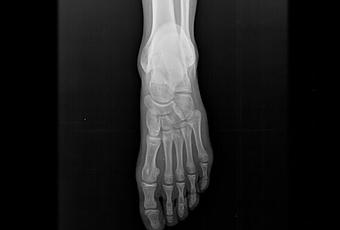

Radiografía anteroposterior y oblicua de pie, donde se observan los siguientes hallazgos:

• Porción distal de tibia y peroné presentan adecuada mineralización ósea, sin evidencia de lesiones líticas o blásticas, ni trazos de fractura.

• Astrágalo, calcáneo y huesos del tarso con densidad ósea normal, sin observar soluciones de continuidad, lesiones líticas o blásticas, sin esclerosis de sus bordes. Adecuada relación entre las estructuras óseas del tarso.

• Se aprecia solución de continuidad de trazo transverso en el quinto metatarsiano a nivel proximal. Resto de los huesos metatarsianos y falanges con adecuada mineralización ósea, sin evidencia de lesiones líticas o blásticas, ni trazos de fractura.

• Articulaciones tarso-metatarsianas, metatarso-falángicas, e interfalángicas presentan espacio conservado y superficies articulares definidas.

• Tejidos blandos con adecuada diferenciación, sin evidencia de alteraciones.

Impresión diagnóstica:

-En el presente estudio que muestra fractura proximal del 5to metatarsiano (fractura de Jones). Resto sin evidencia de alteraciones detectables al momento. A correlacionar con historia clinica del paciente.